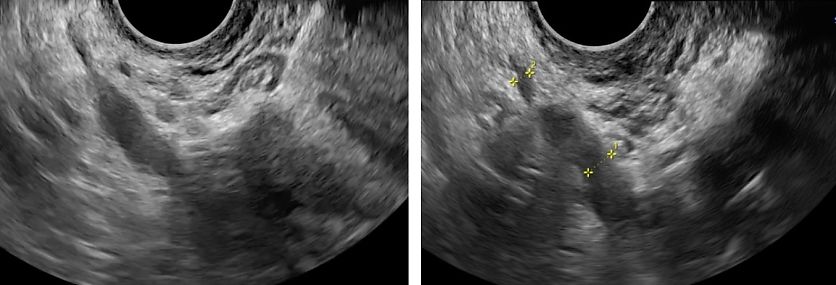

Sacrouterine ligaments (SULs) and torus uterinus

The SULs can be visualized using transverse or oblique parasagittal TVS views and extend from the posterior cervix laterally towards the sacrum. DE nodules appear as hypoechoic, irregular thickening with or without hyperechoic foci (fibrosis or microcalcifications) (Figure 25). The torus uterinus, a fibromuscular transverse band between the SULs, is often affected by midline nodules and should be evaluated alongside SUL disease. Findings include: (1) nodularity or asymmetry of the ligaments; (2) reduced uterine mobility; (3) site-specific tenderness on probe pressure; (4) displacement or elevation of the posterior uterus when the torus is fibrotic.

Leonardi et al. proposed classifying SUL lesions by laterality and depth, which correlates with surgical complexity.40 Reporting the torus uterinus and SULs as distinct structures, despite their anatomical continuity, can support a more accurate description of disease extent and improve preoperative assessment.30

25

Endometriotic nodules within the sacrouterine ligaments.